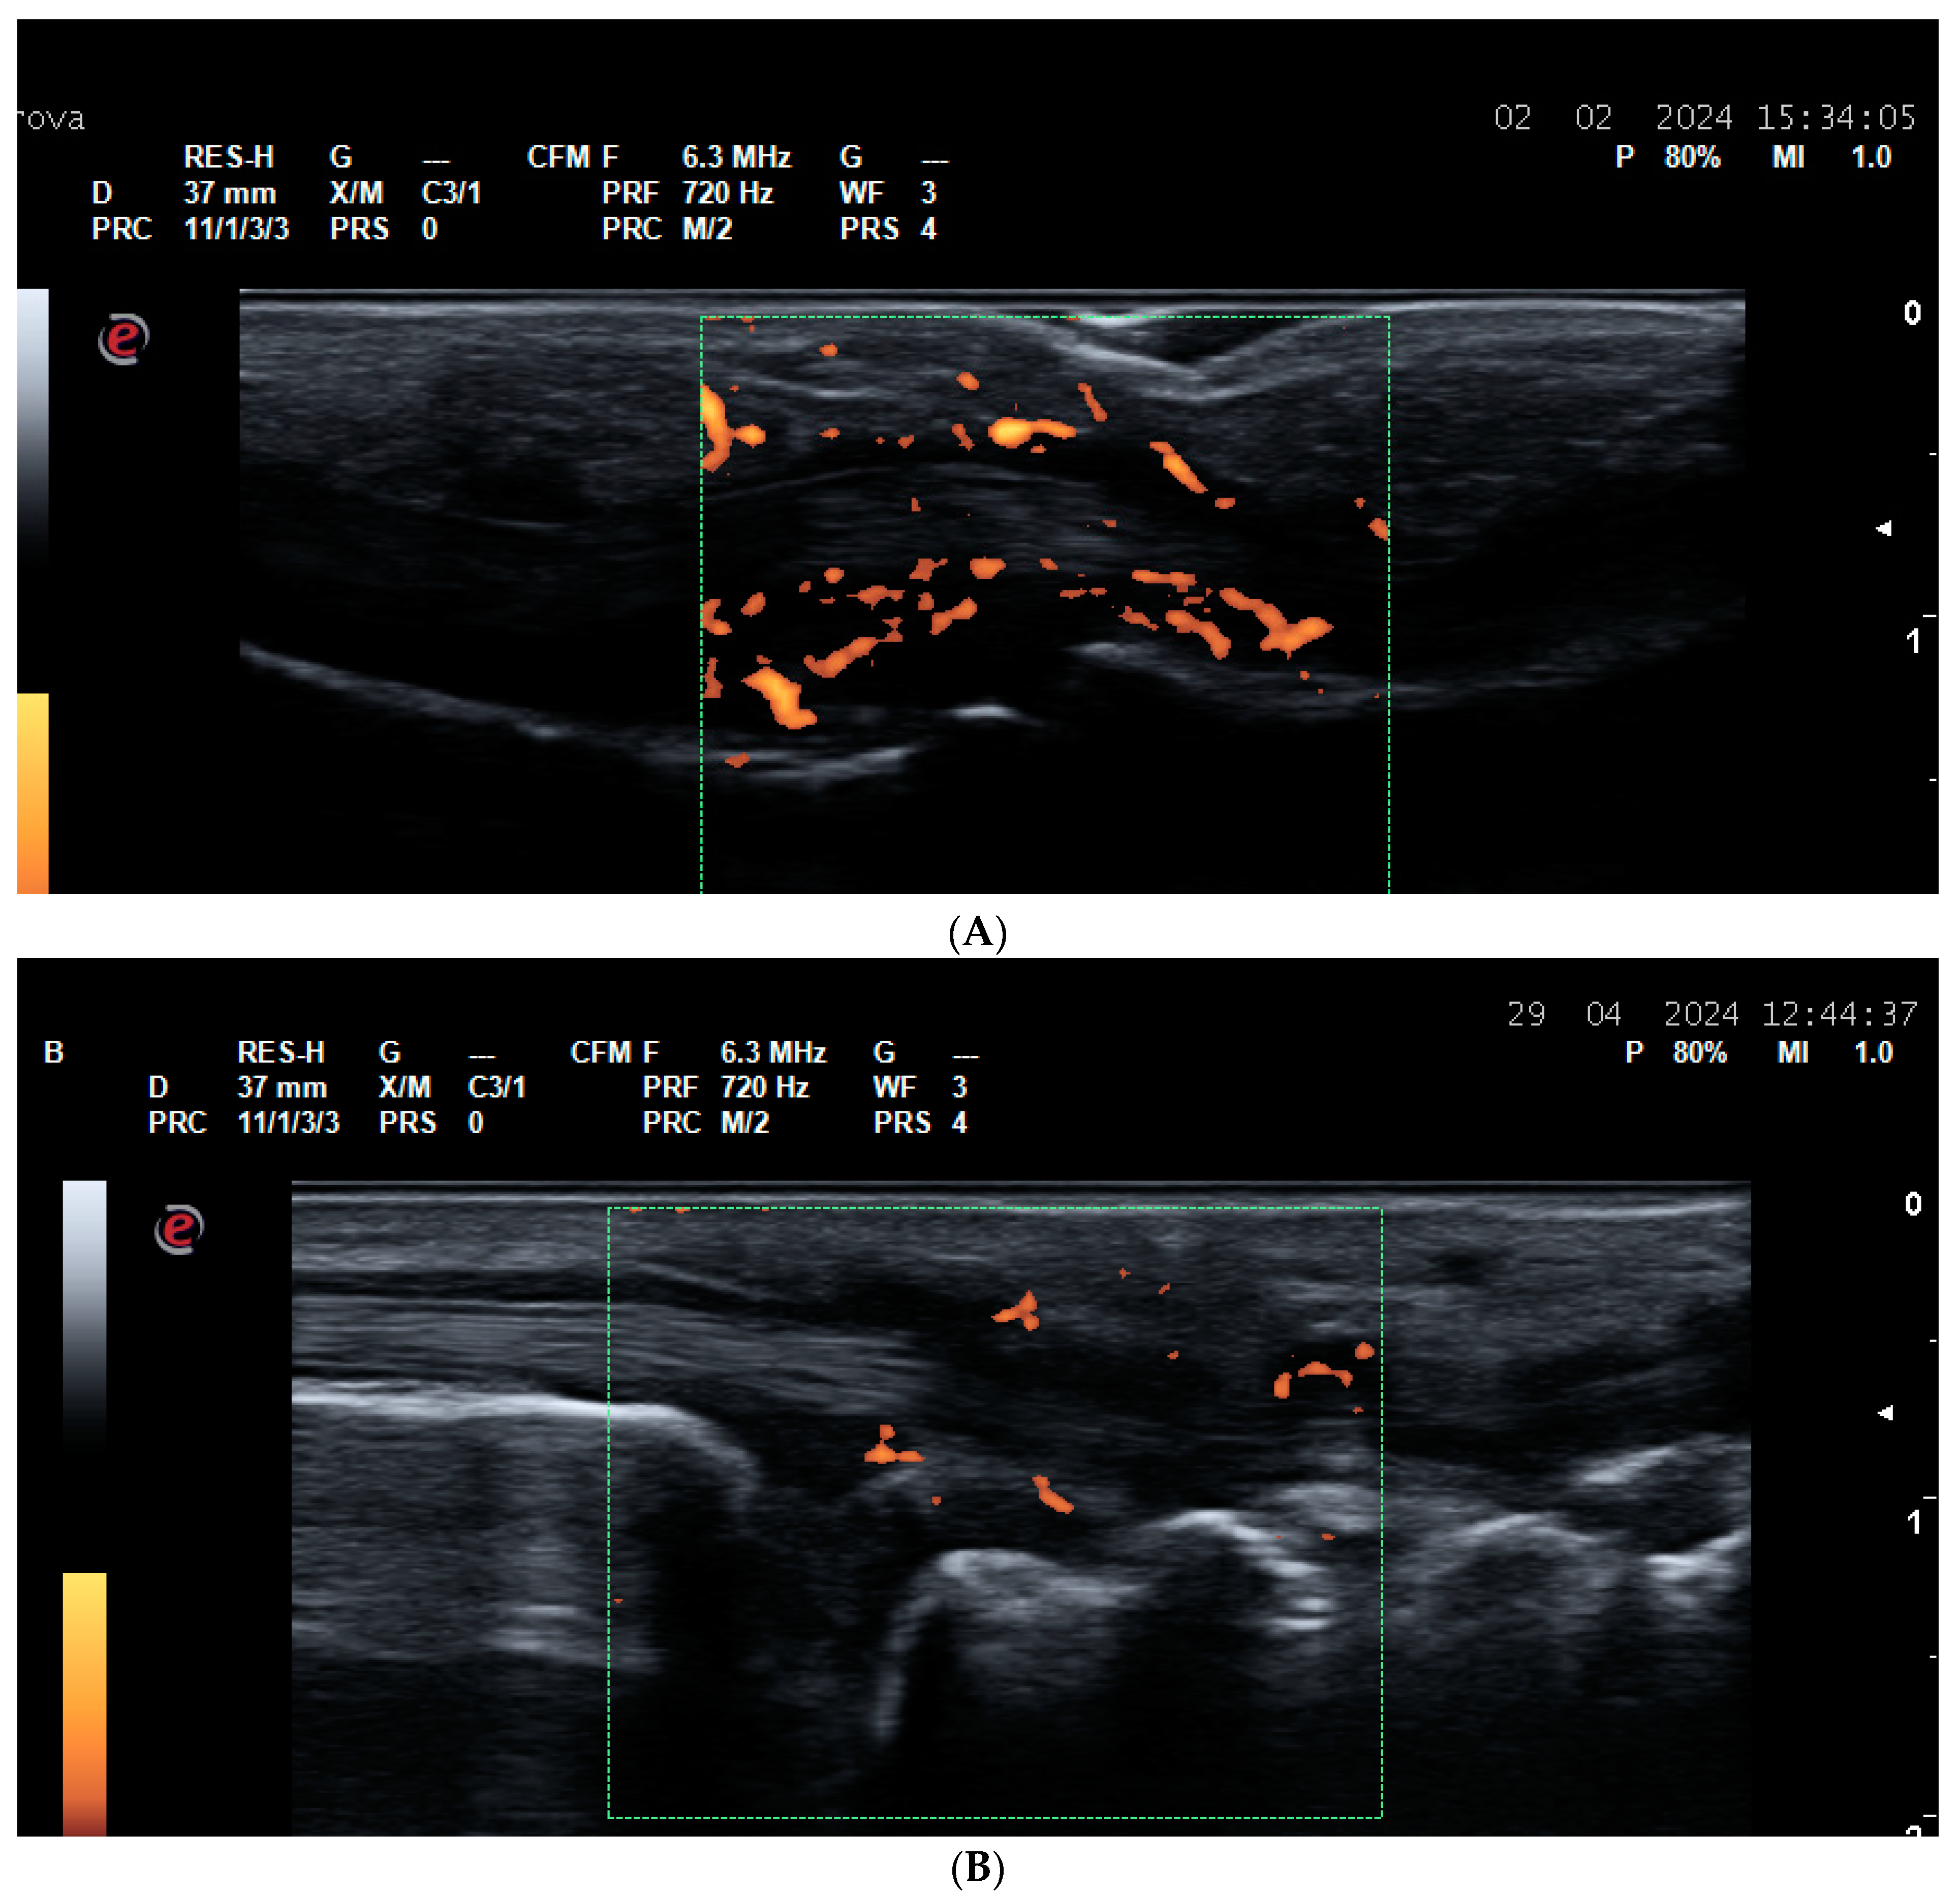

2.2. US for Assessment of Disease Activity and Monitoring Response to Therapy

- Agache, M.; Popescu, C.C.; Enache, L.; Mogoșan, C.; Filippucci, E.; Codreanu, C. Additional Value of Ultrasound in Patients with Psoriatic Arthritis within Treatment Target. J. Clin. Med. 2024, 13, 4567. [Google Scholar] [CrossRef] [PubMed] [PubMed Central]